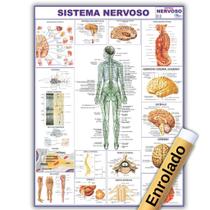

Gente, os modelos anatômicos e simuladores são cópias exatas de diferentes órgãos do corpo de humanos e dos animais, que servem pra professores e outros profissionais mostrarem como funcionam os sistemas do corpo. Eles imitam a estrutura interna e externa do organismo e também são usados pra treinamentos práticos! Quer saber mais sobre eles? Vem comigo que eu te conto:

Gente, os modelos anatômicos e simuladores são cópias exatas de diferentes órgãos do corpo de humanos e dos animais, que servem pra professores e outros profissionais mostrarem como funcionam os sistemas do corpo. Eles imitam a estrutura interna e externa do organismo e também são usados pra treinamentos práticos! Quer saber mais sobre eles? Vem comigo que eu te conto:

- Olha, os modelos anatômicos e simuladores são usados em áreas como Medicina, Enfermagem, Fisioterapia e Veterinária pra imitar órgãos como o coração, rins, útero, olhos, cérebro, as articulações e até o esqueleto inteiro.

- Esses modelos são feitos de resina ou de propiletileno, que é um plástico mais duro, e são desmontáveis, pra apontar todos os detalhes dos órgãos, como camadas, veias e nervos.

- Agora, o simulador pode imitar adultos, idosos e crianças de corpo inteiro ou apenas uma parte dele, como a perna, a cabeça, o pé ou o tronco.

- E tem modelos que vêm com recursos digitais, como programas que reproduzem situações de risco de vida e que indicam quando o procedimento está sendo feito da forma certa. Legal!

Aqui no Magazine Luiza tem vários modelos anatômicos e simuladores. Vem ver!